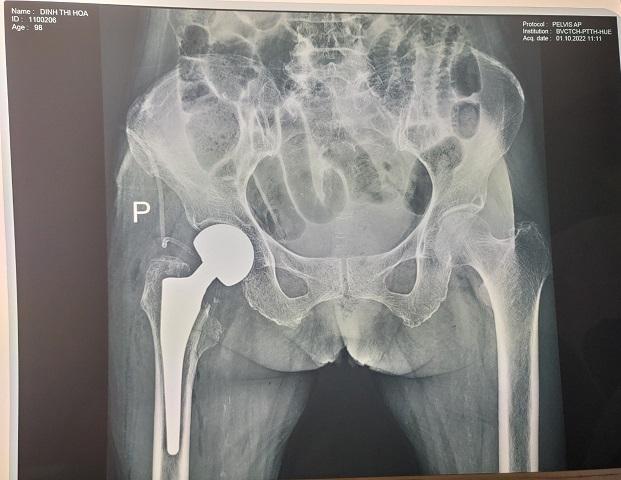

Được phẫu thuật thay khớp háng phải bán phần không cement

Hình ảnh : Phim XQ trước và sau mổ thay khớp háng phải.